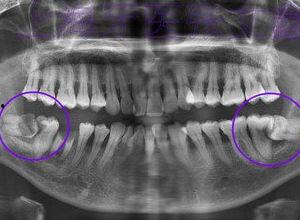

磨牙,医学上称为“夜磨牙症”,是一种常见的睡眠障碍。据统计,全球约有10%到30%的人有磨牙的经历。磨牙的原因有很多,比如压力、焦虑、牙齿排列不齐、咬合不正等。别小看了磨牙,长期下去可能会对牙齿、颚骨和听力造成伤害。

磨牙不仅会影响你的睡眠质量,还会对你的牙齿造成严重伤害。长时间磨牙会导致牙齿表面磨损,甚至出现牙齿断裂、牙根暴露等问题。更严重的是,磨牙还可能引发颚骨关节疾病,让你在咀嚼时感到疼痛。

如果你的磨牙是因为牙齿排列不齐或咬合不正导致的,那么建议你去看牙医。牙医会为你制定合适的治疗方案,比如矫正牙齿、调整咬合等。